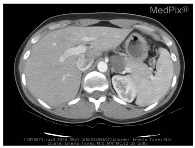

| Image | Category | Generated and Ground Truth Questions |

|---|---|---|

![]() | Plane | what plane is this image obtained? what plane is this image blood-samples? Is this image of a saggital plane? |